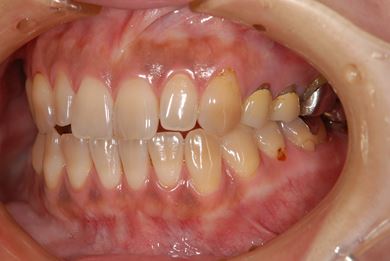

治療前

• 治療前